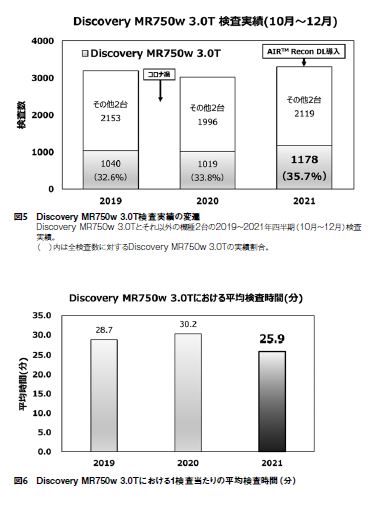

2. AIR™ Recon DL導入機種の検査数増加

AIR™ Recon DLが実装されているDiscoveryMR750w 3.0Tの直近数年間の10月~12月期の検査実績を図5に示す。コロナ禍によって外来患者の受診控えや入院患者の制限により、2020年は前年に比較して約5%の検査実績減少となった。AIR™ Recon DLが導入された2021年は新型コロナウィルスへの警戒感の緩和もあるが、大幅な検査実績の増加となった。図5の( )内は全検査数に対するDiscovery MR750w3.0Tにおける検査実績の割合であるが、2019、2020年に比較して2021年は2~3%検査数が増加している。また、図6のDiscovery MR750w3.0Tにおける1検査当たりの平均検査時間では例年は28分~30分を要していたのに対し、2021年は平均約26分に短縮されている。以上のように検査ワークフローの改善により当該機種の一日当たりの検査数が増え、予約枠圧迫の改善や時間外業務の減少などの病院経営への貢献にも役立っている。